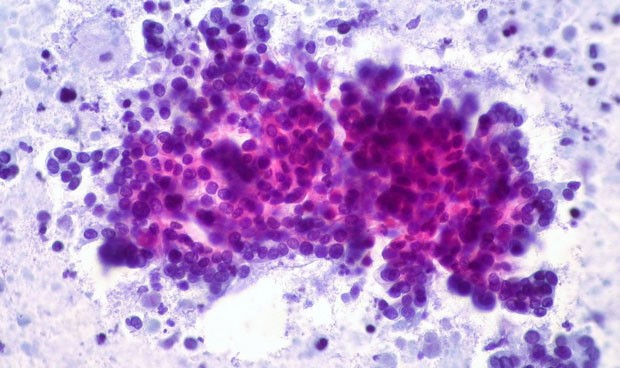

Dividen el cáncer de páncreas en dos tipos según su respuesta a la terapia

La clasificación de los tumores predice la respuesta al tratamiento.

Una investigación del Centro Integral del Cáncer Lineberger de la Universidad de Carolina del Norte (UNC), en EEUU, podría ayudar a predecir la resistencia a los tratamientos para el cáncer de páncreas en base a la clasificación de los subtipos del tumor.

En 2015, los investigadores de UNC Lineberger descubrieron dos subtipos principales de cáncer de páncreas basados en las características moleculares y genéticas de la enfermedad. Sin embargo, otros grupos de investigación informaron de diferentes sistemas de clasificación con tres y cuatro subtipos. Así, los investigadores consideraban que no había consenso sobre cuál de los sistemas propuestos era óptimo para la toma de decisiones clínicas.

Después de analizar cinco estudios independientes, "encontramos que este sistema más simple, de dos subtipos, explicaba mejor las respuestas al tratamiento y los resultados de supervivencia", ha señalado Rashid. En los ensayos, los tumores de tipo basal no mostraron respuesta al folfirinox, la terapia estándar que combina cinco agentes de quimioterapia, o un tratamiento que utilizó folfirinox como elemento central. El otro tipo de tumor, al que llamaron "clásico", mostró una mejor respuesta a este tratamiento. "Queremos saber qué terapias son las mejores para el paciente, de manera que podamos maximizar la respuesta y la calidad de vida", ha apuntado Yeh. "Para el cáncer de páncreas, donde el tiempo es más limitado, esto se vuelve aún más importante."